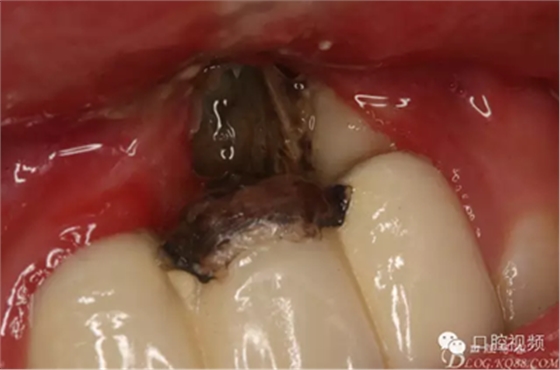

圖1.21唇側(cè)牙齦潰爛。牙槽骨暴露成灰褐色,22近中根面外露。